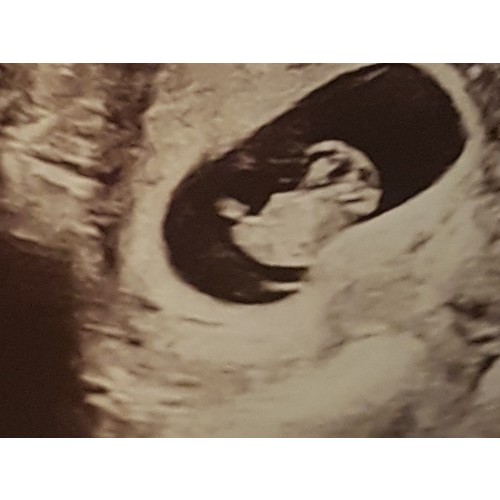

Oooh super,hier net hetzelfde.Om 16 u eerste echo!Zo spannend 鉂わ笍